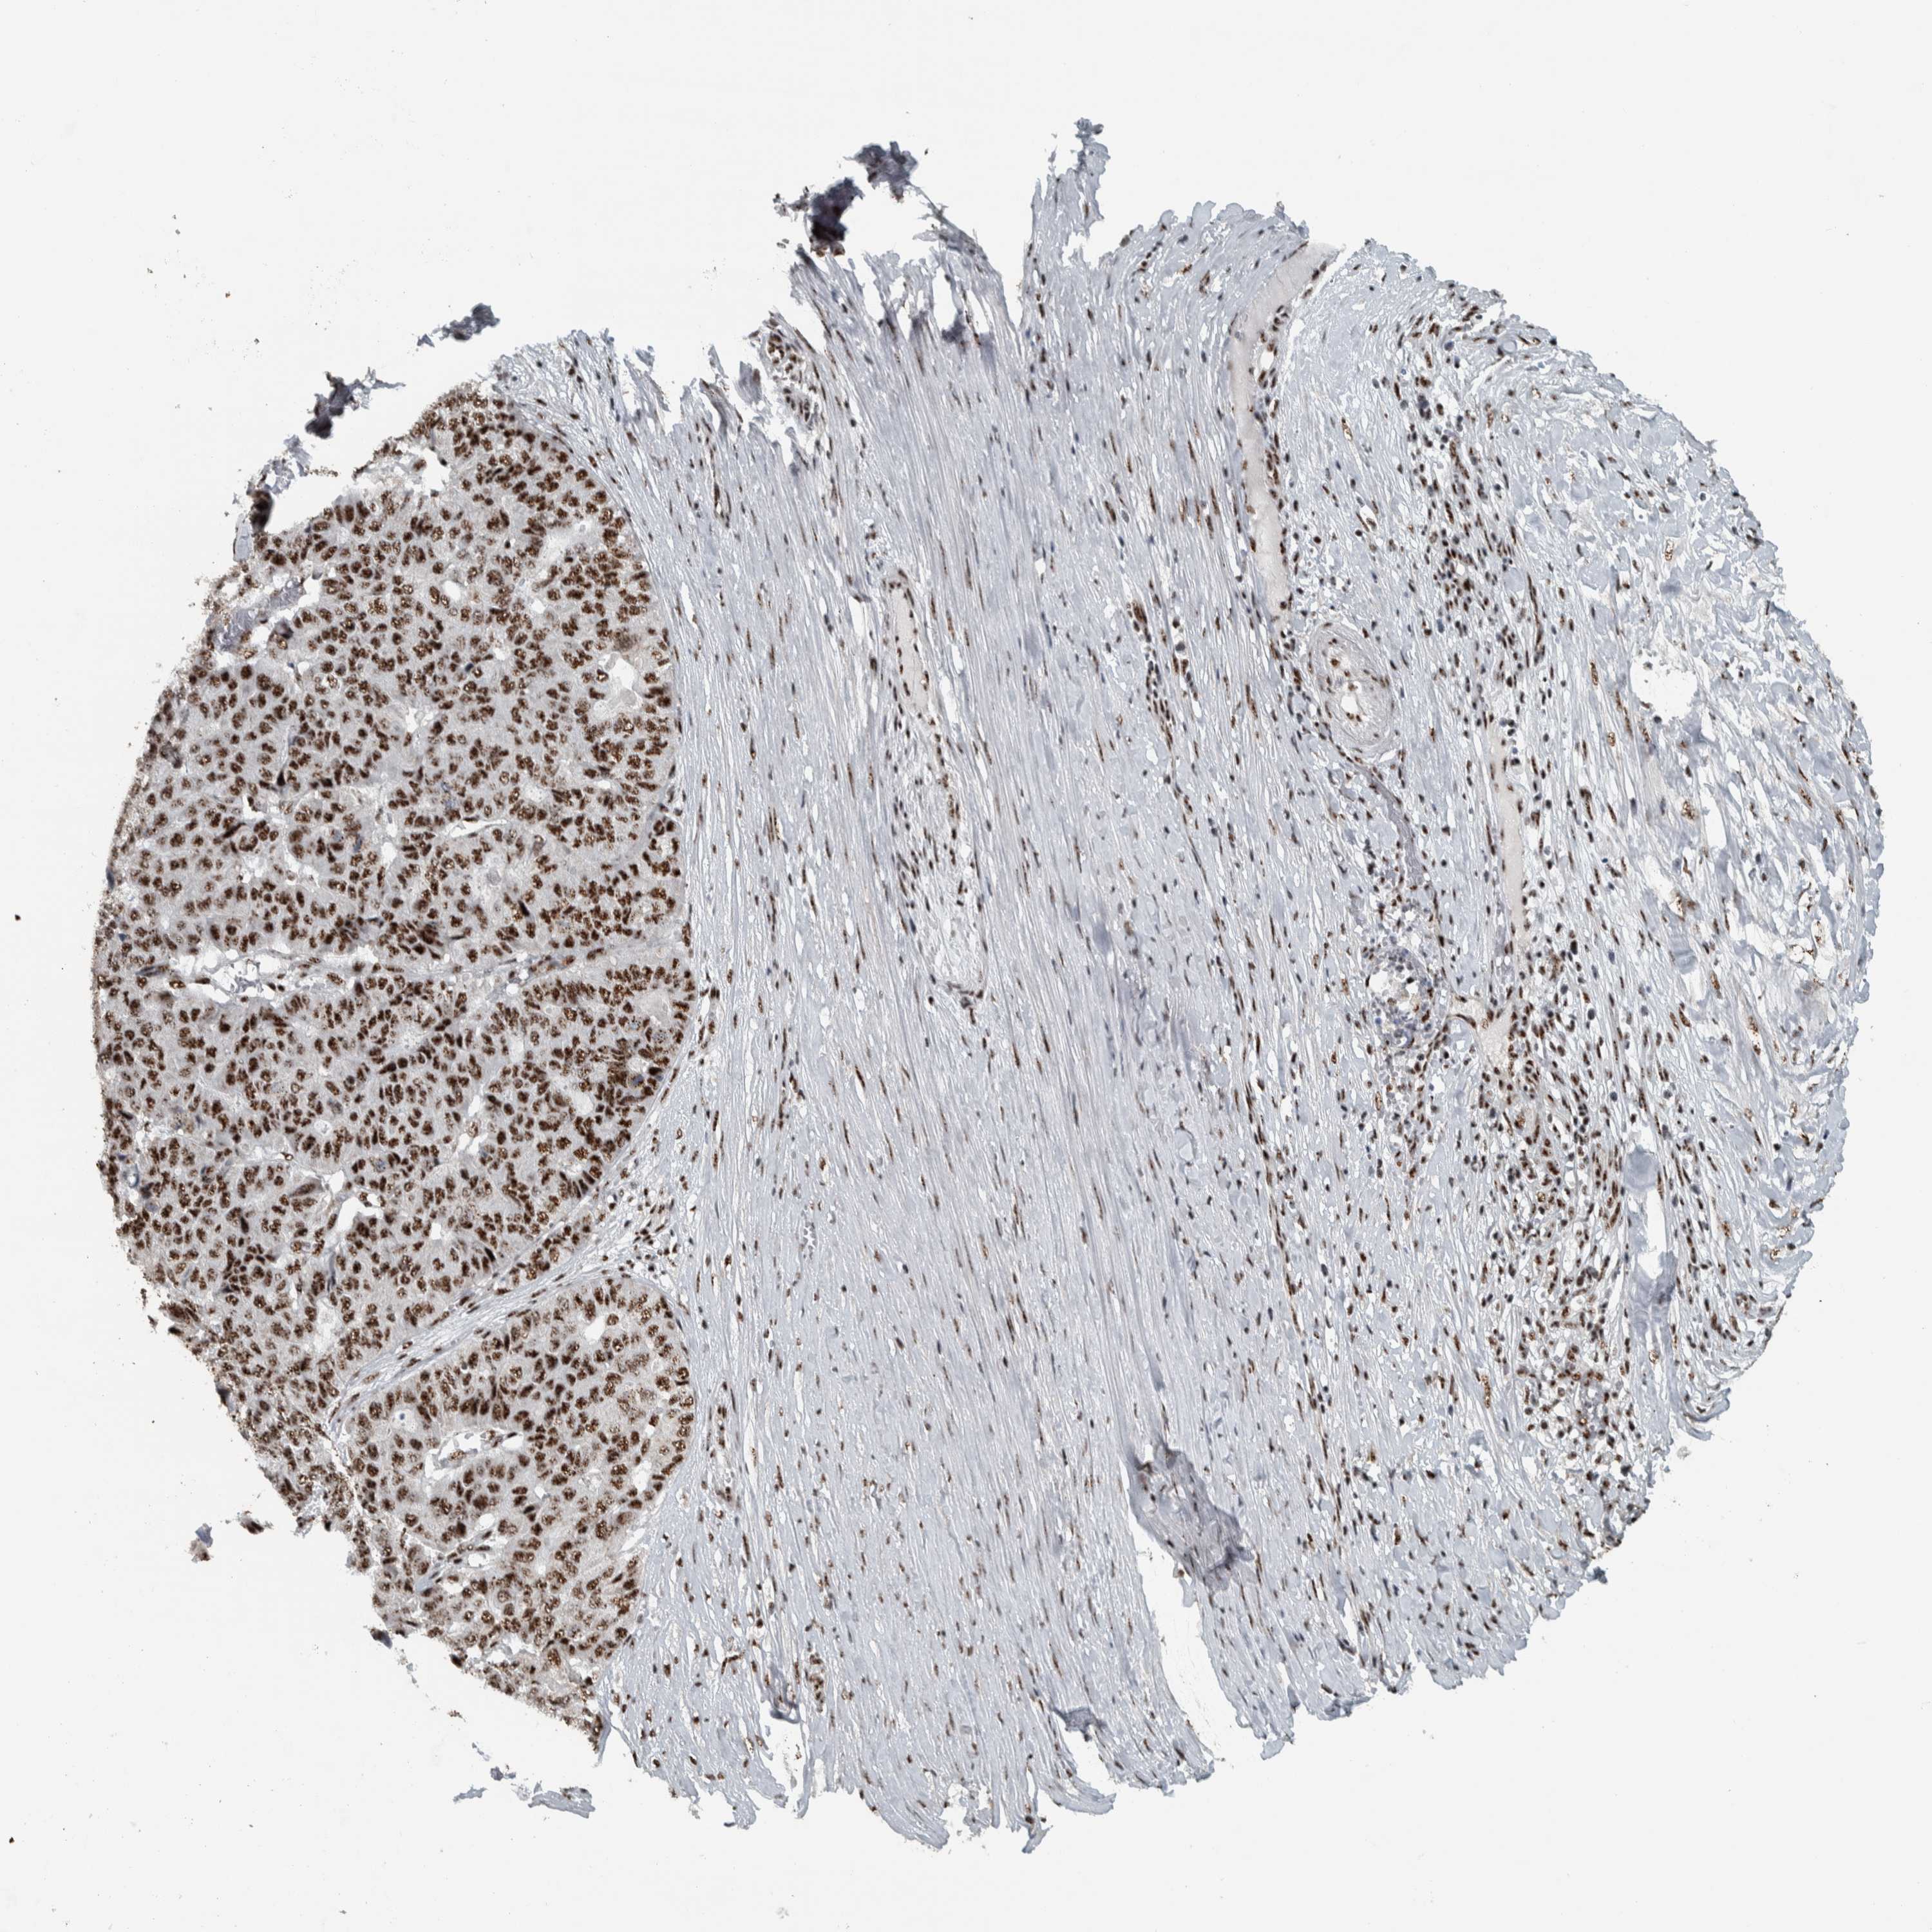

PANCREATIC CANCER - Protein expressioni

A mouse-over function shows sample information and annotation data. Click on an image to view it in a full screen mode. Samples can be filtered based on level of antibody staining by selecting one or several of the following categories: high, medium, low and not detected. The assay and annotation is described here.

Note that samples used for immunohistochemistry by the Human Protein Atlas do not correspond to samples in the TCGA dataset.

Antibody stainingi

Antibody staining in the annotated cell types in the current human tissue is reported as not detected, low, medium, or high, based on conventional immunohistochemistry profiling in selected tissues. This score is based on the combination of the staining intensity and fraction of stained cells.

Each image is clickable and will lead to virtual microscopy that enables deeper exploration of all samples and also displays staining intensity scores, fraction scores and subcellular localization as well as patient and tissue information for each sample.

Antibody HPA023535

Staining

High

Medium

Low

Not detected

Intensity

Strong

Moderate

Weak

Negative

Quantity

>75%

75%-25%

<25%

None

Location

Nuclear

Cytoplasmic/membranous

Cytoplasmic/membranous,nuclear

Adenocarcinoma, NOS